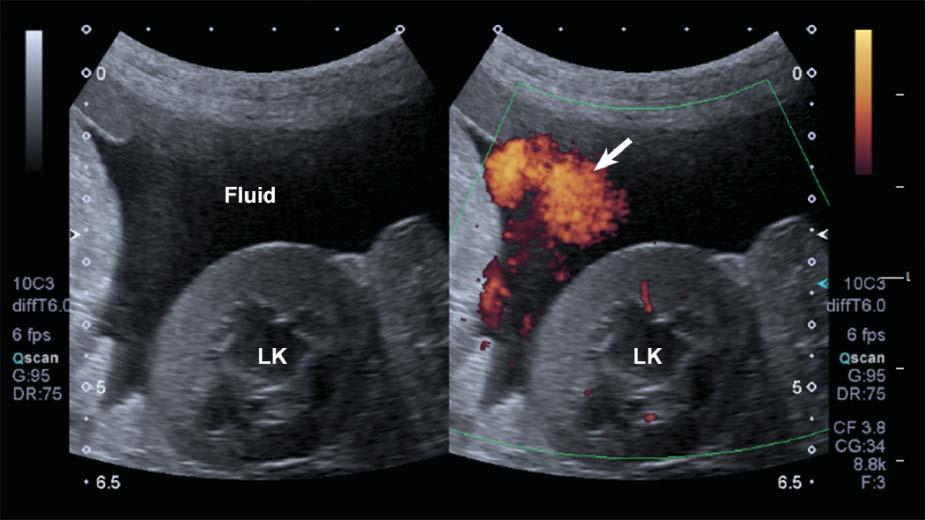

Rapidmovementofthepatient’sbody,ofastructural component(e.g.,heartorarterialpulsation),orofthe probemightleadtoDopplershiftsbeinginterpreted bythesystemasbloodflow.Aspuriousappearance

ofbloodflowisdisplayed,limitingtheassessmentof truevessels.Thisartifacttendstobemoreapparentin fluid-filledstructuresandwithascites(Figure1.25).

Figure1.25. Flash. SpuriousechoesoftenappearwhenusingpowerDopplerinmovingpatientsorwhenascitesispresent, limitingtheassessmentthetissueperfusioninthesecases.LK,leftkidney.